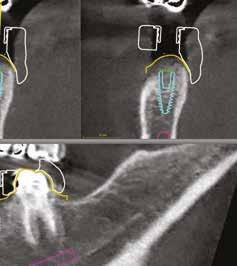

A korai harmicas éveiben járó hölgy rendelőnkbe érkezésének oka a jobb felső nagymetsző fog bizonytalan érzkenysége, elmondása alapján gyermekkorában trauma érte a felső frontrégiót. A frakturált klinikai koronákat kompozittöméssel helyreállították, egyéb kezelést akkor nem tartottak szükségesnek. Az utóbbi hónapokban tapasztalt érzékenység miatt kereste fel rendelőnket. A klinikai vizsgálat (1. és 2. kép) és a CBCT felvétel (3. kép) alapján diagnosztizált külső gyökérreszorpció megoldására a fog eltávolítását, implantátum

bukkális 1. kép: Kiindulási állapot, 2020. január. 3. kép: Kiindulási CBCT felvétel. 2. kép: Kiindulási állapot a palatinális oldal felől.